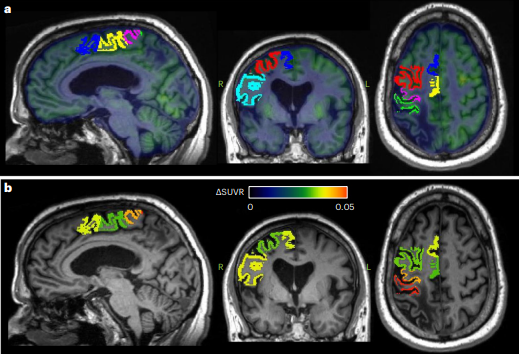

La investigación de Baker et al. (2023) se enfocó en una novedosa aproximación: la estimulación continua del núcleo dentado cerebeloso para modular la actividad neural y la excitabilidad cortical ipsilesional.

Esta hipótesis se basó en investigaciones electrofisiológicas de la vía cerebelo-talámo-cortical. En esa misma línea, se sostiene que la reorganización cortical y formación de sinapsis destacan por su relevancia en la recuperación de la motricidad. Respecto a dicha hipótesis, se aplicó en un grupo de 12 sobrevivientes de ACV, con discapacidad moderada a severa en el miembro superior.